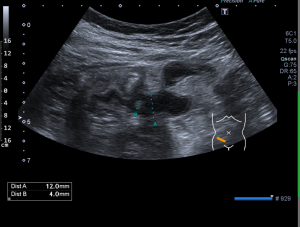

Vyšetření provádí erudovaný lékař, který pro danou vyšetřovanou oblast zvolí vhodnou ultrazvukovou sondu a nastaví optimální parametry přístroje. Pacient při vyšetření leží na vyšetřovacím stole a dodržuje pokyny lékaře. Nejčastěji se vyšetření provádí vleže na zádech, na břiše nebo na boku. Kůže pacienta se ve vyšetřované oblasti pokrývá vrstvou gelu pro sonografii. Lékař plynule pohybuje po pacientově těle ve vyšetřované oblasti ultrazvukovou sondou a při tom sleduje obraz na monitoru. Vyšetření se provádí v různých rovinách daných postavením sondy, někdy i v různých polohách pacienta. Během vyšetření lékař v případě potřeby provádí různá měření. Při vyšetření asistuje vyškolená sestra, která pomáhá především s odstrojením a uložením pacienta, provádí administrativní úkony a řídí objednávání pacientů. Před vyšetřením sestra nebo lékař vysvětlí pacientovi stručně, jak vyšetření probíhá a co je jeho cílem, eventuelně rozptýlí případné obavy pacienta z vyšetření. Na závěr vyšetření pak lékař pacientovi co nejsrozumitelněji vysvětlí zjištěný nález, jeho závažnost a případné další důsledky. Obrazová dokumentace je zhotovena tiskem na speciální papír, eventuelně je provedena digitální archivace obrazu.

Na našem pracovišti provádí lékaři radiodiagnostického oddělení ultrazvukové vyšetření břicha, třísel, axil, krku a povrchových rezistencí.